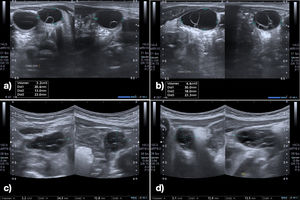

El estudio mostró niveles elevados de FSH, LH y estradiol (fig. 2), y ecografía abdominal con ovarios aumentados y lesiones quísticas (tabla 1).

| Ecografía ovario izquierdo (cm3) | 3,2 | 2,2 | No se visualiza |

| Ecografía ovario derecho (cm3) | 6,6 | 2,1 | No se visualiza |

La paciente evolucionó con resolución espontánea, normalización hormonal y desaparición de quistes a los 11 meses de edad (corregida 7 meses).